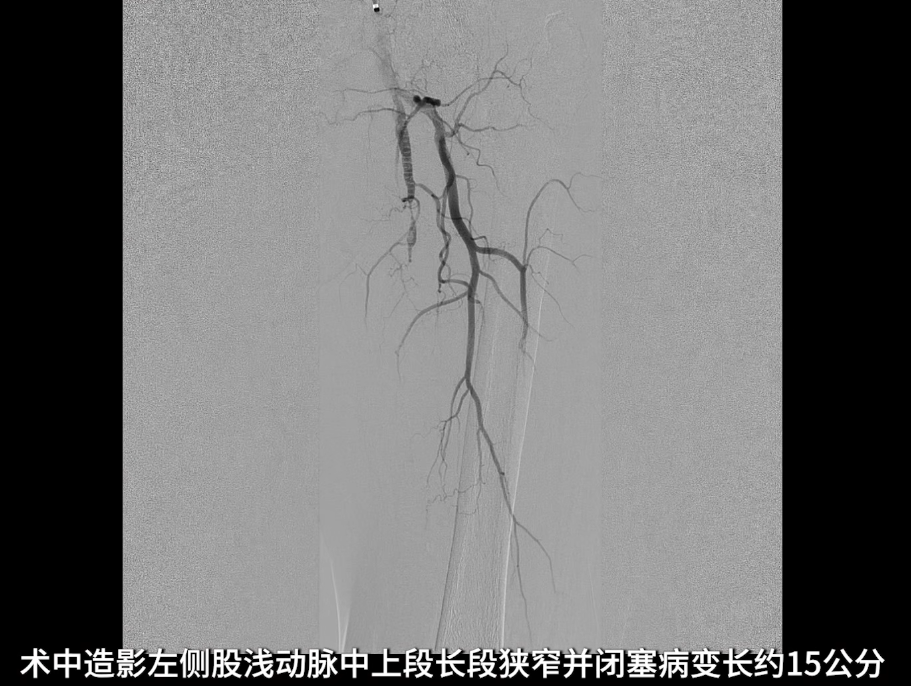

术中造影确认病变

左侧股浅动脉中上段明确长段狭窄并闭塞,病变长度约15cm,股浅动脉远段至腘动脉管腔通畅。